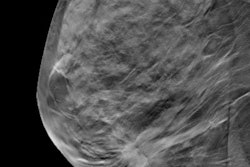

The two offerings are called Mammogram+ and Mammogram+ Heart. Mammogram+ is designed to identify breast cancer earlier and to offer women insights into their breast density and lifetime risk. It replaces the company's Personalized Breast Cancer Detection program.

Mammogram+ Heart incorporates an AI-based assessment of breast arterial calcification on mammography imaging -- an emerging clinical marker linked to cardiovascular risk in women. The package allows for detection of both breast cancer and early signs of heart disease in a single appointment, according to SimonMed.